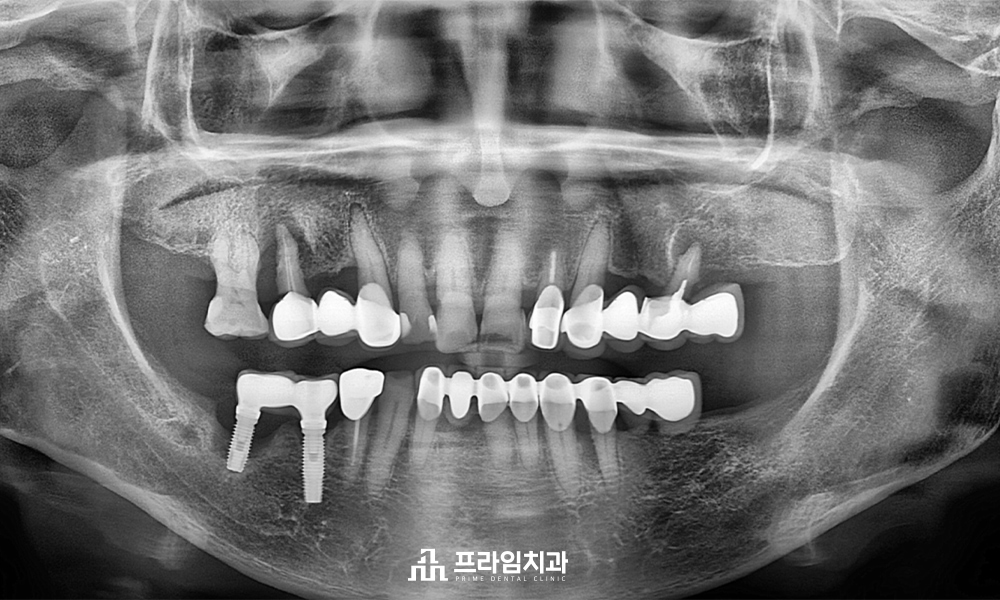

전체적인 파노라마 사진을 촬영한 결과,

왼쪽에서는 이미 어금니가 상실되어

브릿지 형태로 치료가 되어 힘을 받는

치아들의 상태가 좋지 않음을

확인할 수 있었습니다.

오른쪽에서는 기존 아래 임플란트 주위와

위쪽의 자연 치아 주위에서 잇몸뼈가

많이 소실되어 예후가 좋지 않은

상황이 관찰되었습니다.

따라서 예후가 좋지 않은 치아들은

모두 발치한 후 임플란트 식립 계획을

세우기로 했습니다.